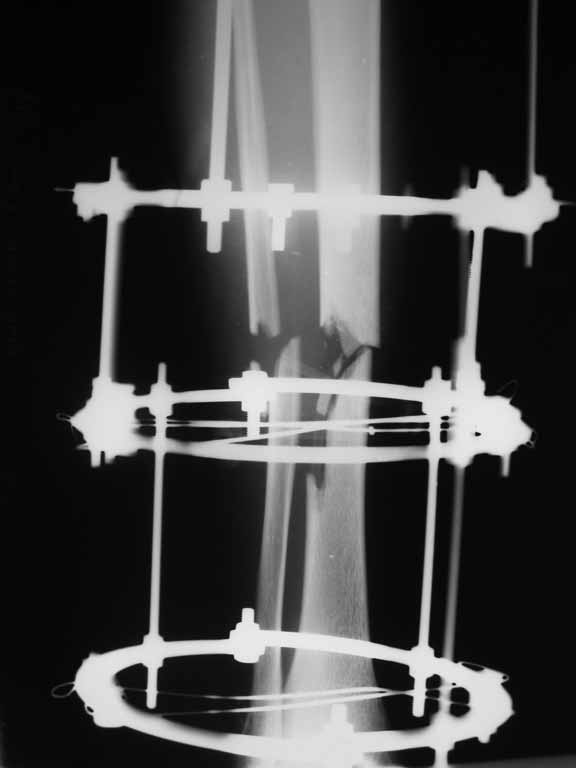

Re: Перелом большеберцовой кости с дефектом дифизарной части

Извините, не загрузились сразу все рентгенограммы.

Внедрение одного отломка в другой приведет к укорочению. Резекция с выращиванием резко удлинит срок лечения, вероятно, потребуются еще какие-то операции после завершения дистракции... А самое главное, это избыточные действия. Ведь дефект не сегментарный, краевой контакт есть.

Вполне достаточно закрытого интрамедуллярного остеосинтеза без открытых вмешательств в зоне стыка. Конечно, с рассверливанием. Если есть опасения насчет инфекции, то на гвоздь нанести цемент с ванкомицином.

Гвоздь тут будет эндопротезом диафиза на достаточное время для образования сращения в зоне имеющегося небольшого контакта. И далее страховкой от рефрактур.

Вот пример, тоже открытый перелом, первичный дефект, пробыл в аппарате 5 мес. Титановый гвоздь, сразу динамический, без покрытия. Больше не делали ничего.